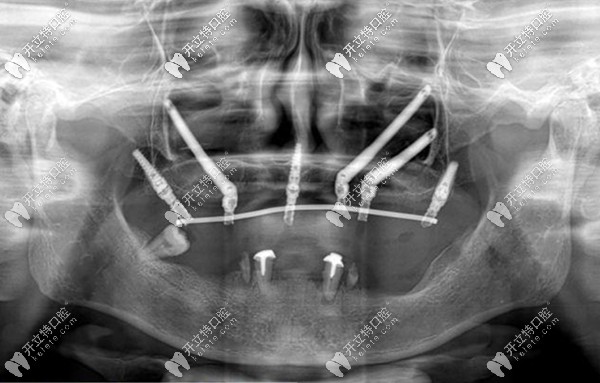

穿顴穿翼種植體在面部骨骼的分布圖